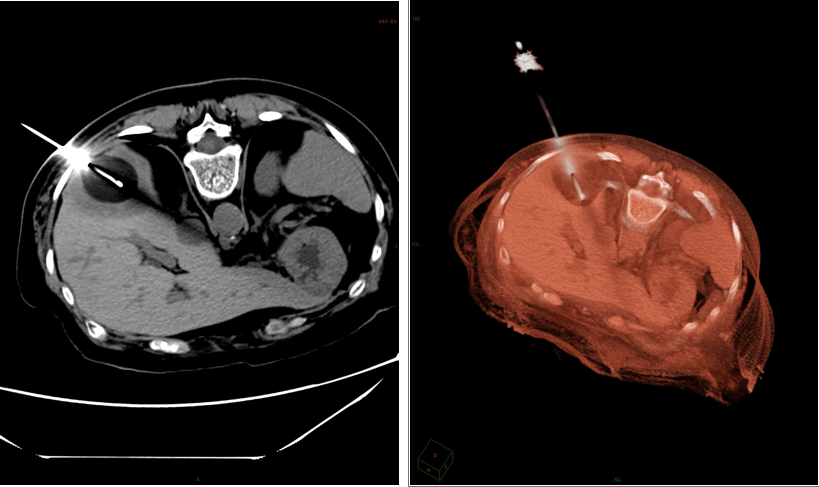

Cryoablation of liver metastases

The interventional radiologist uses real-time imaging to guide a needle / catheter to the tumor lesion.